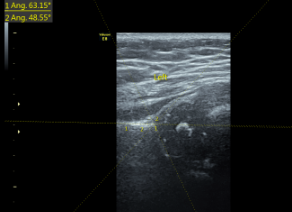

髋关节发育不良↓

正常髋关节↓